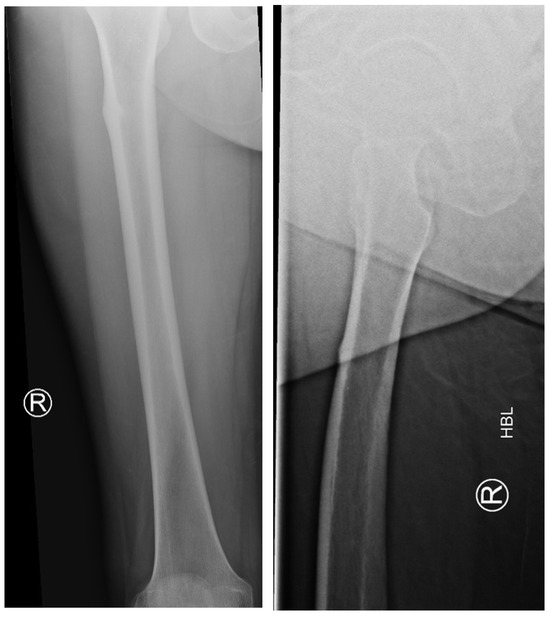

The following radiographs present the initial radiographs from the day of injury along with those obtained during the final OPD follow-up of the patient. The sequence presents radiographs demonstrating full radiological union (Scheme 1 and Scheme 2) and X-rays with no evidence of fracture healing at the final OPD follow-up (Scheme 3 and Scheme 4).

Scheme 1. X-ray of right hip AP view (left) and lateral view of right proximal femur (right) of atypical subtrochanteric fracture—September 2023.

Jcm 14 02858 sch001